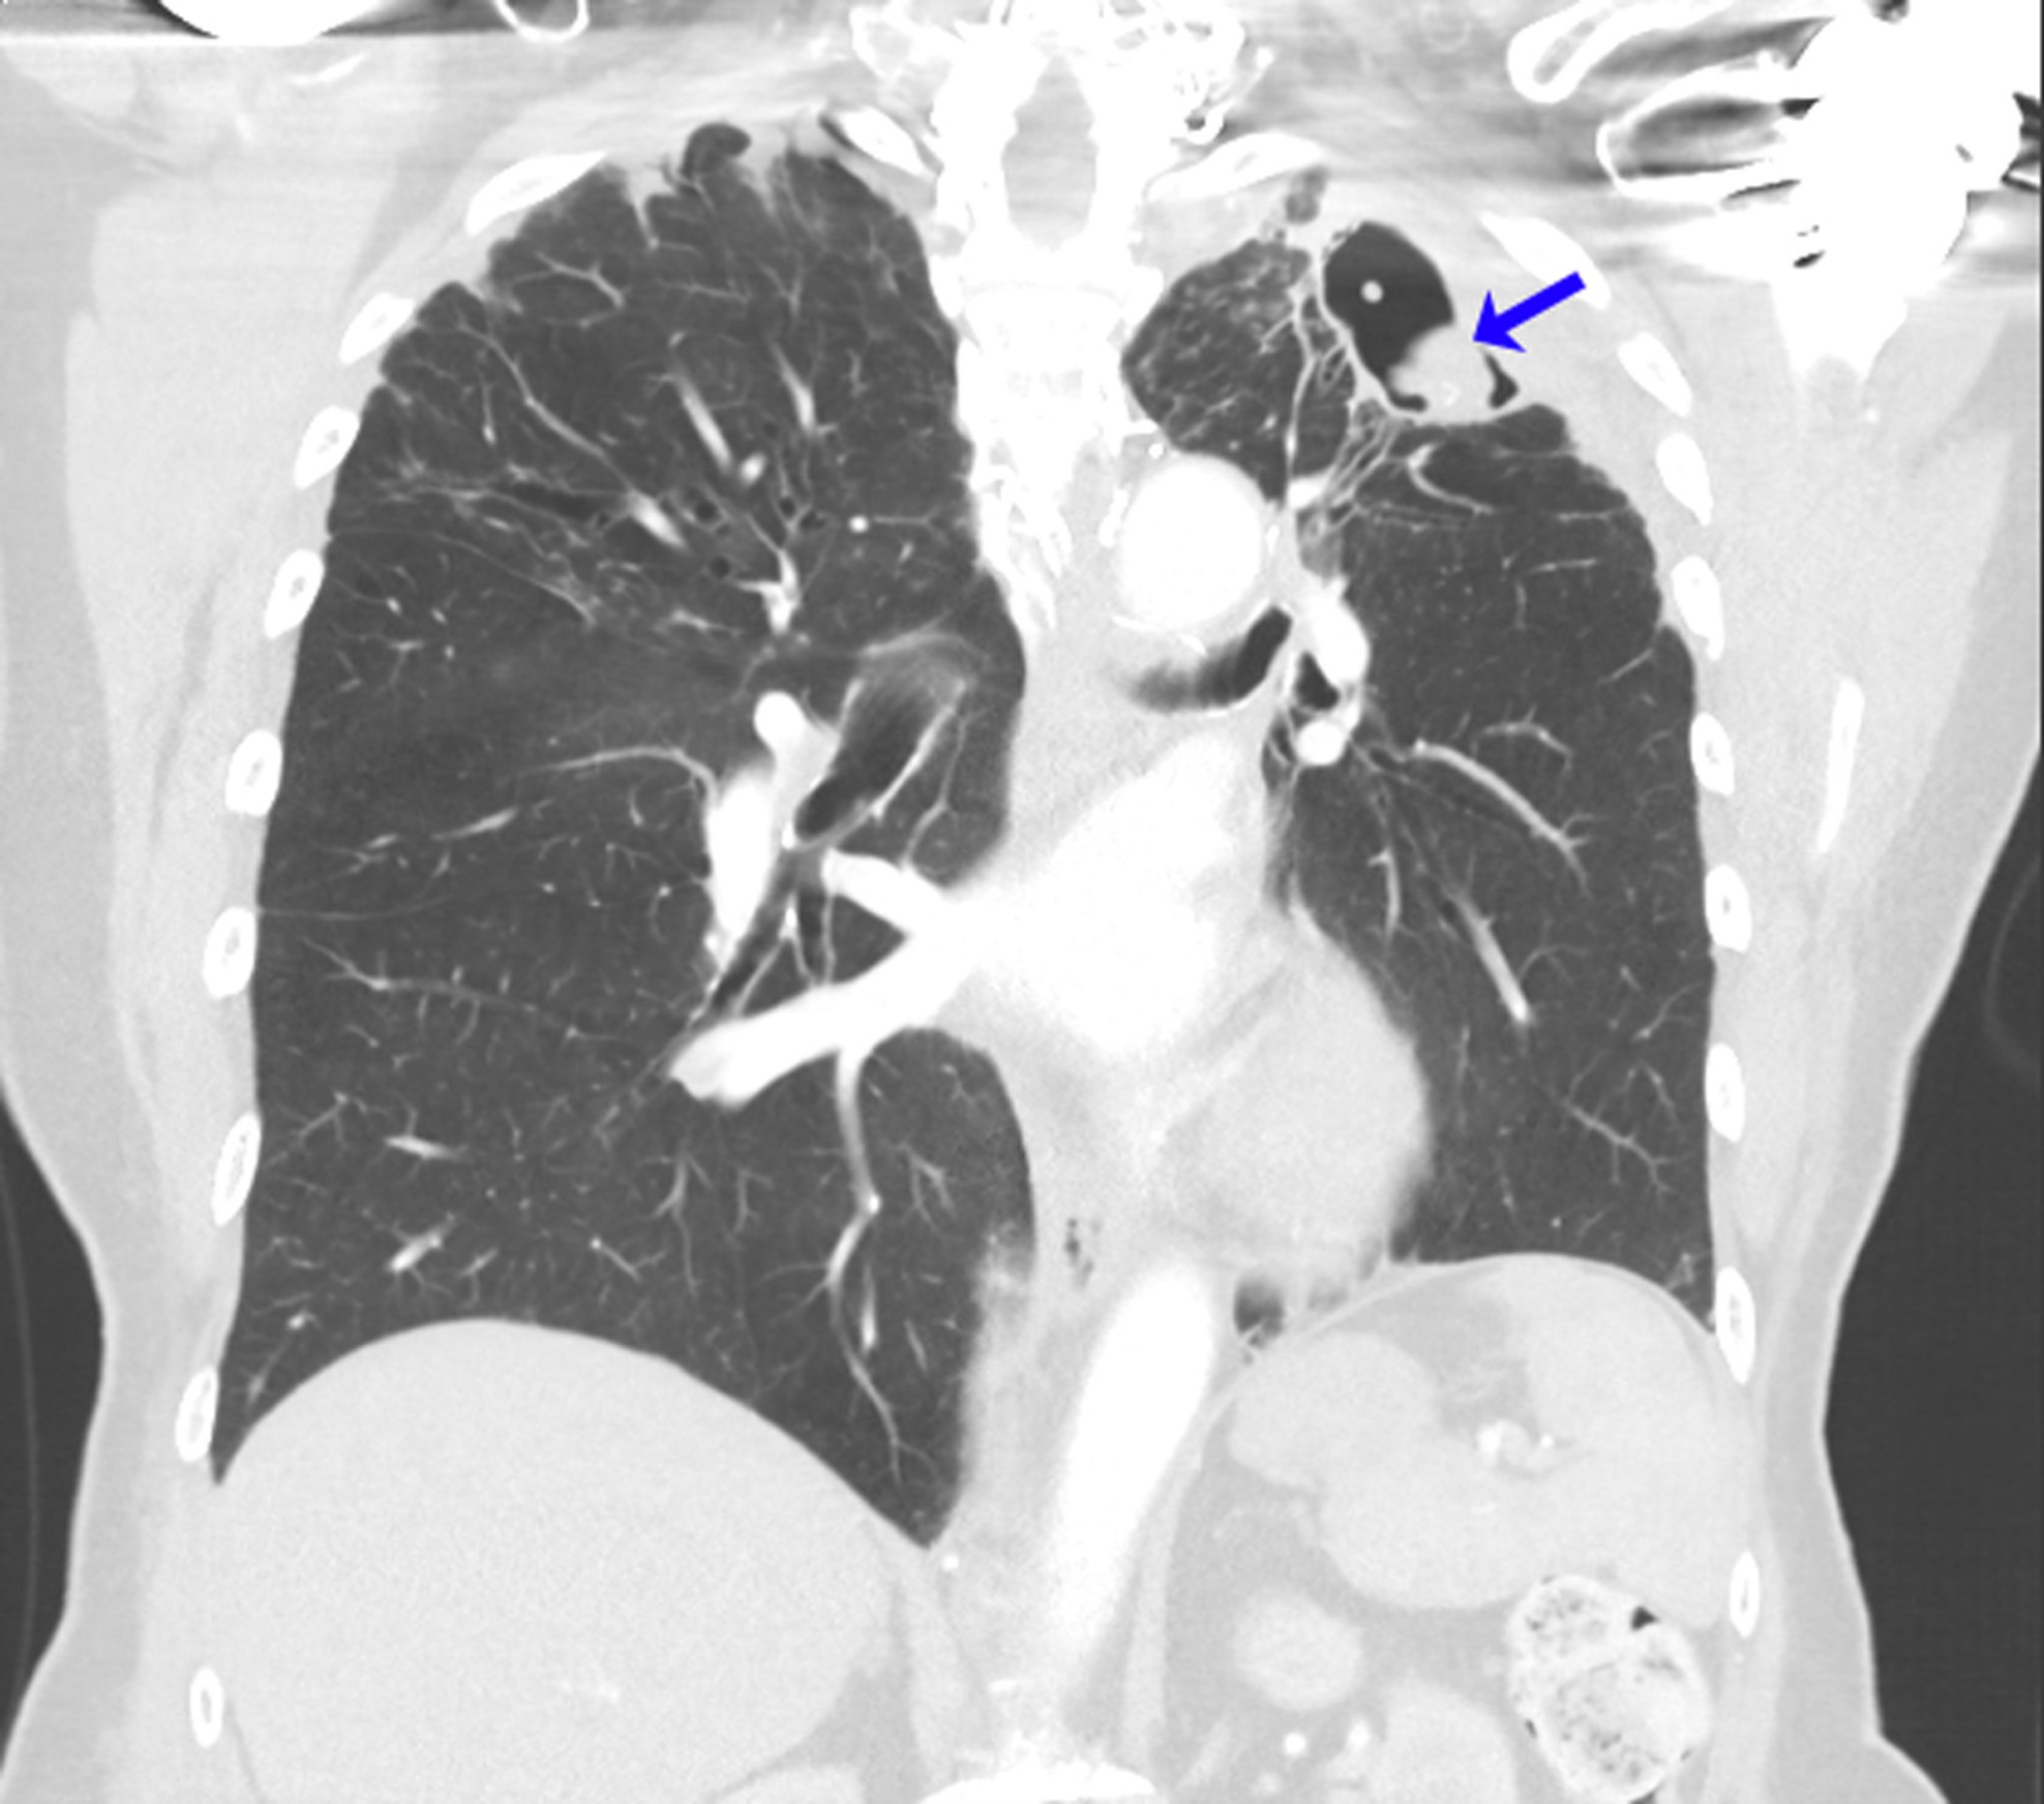

Aspergilloma ricorrente

Questa scansione TC mostra i polmoni di una persona con una storia di aspergillosi broncopolmonare allergica nel contesto di un asma. Dopo lobectomia superiore sinistra per aspergilloma, si è sviluppato un micetoma ricorrente all'apice del polmone sinistro (freccia).

Image courtesy of Paschalis Vergidis, MD, MSc.